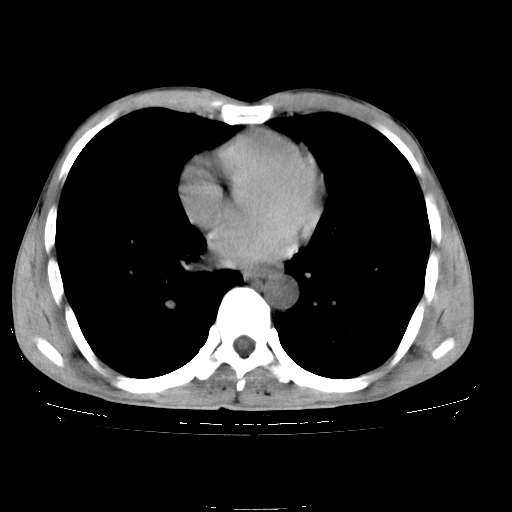

以下是引用yangyudong333在2008-4-29 5:38:00的发言:[br]比较典型的矽肺结节.支持[br]诊断依据:[br] 1.x线表现:[br] ①典型矽肺为多发直径 1~3mm 小结节,即矽结节,由胶原纤维和硅尘构成,可融合成团块,好发于上肺。[br] ②团块周围常有肺大泡。[br] ③胸内淋巴结增大、钙化。如肺门淋巴结呈蛋壳样钙化有助于与其他尘肺区别。[br] ④胸膜常广泛粘连、增厚。[br] 2.ct表现[br] ①两肺散在大小较为一致的小结节影,其密度较高,边界清楚。[br] ②小结节可融合为较大团块影,直径约 1cm ,甚至可达 10cm以上,易发生在上叶。[br] ③小结节周围常并有小叶中心气肿或弥漫性肺气肿。

以下是引用liuyue在2008-4-28 22:30:00的发言:[br]比较典型的矽肺结节.[br]请结合临床及化验除外矽肺合并肺结核之可能.